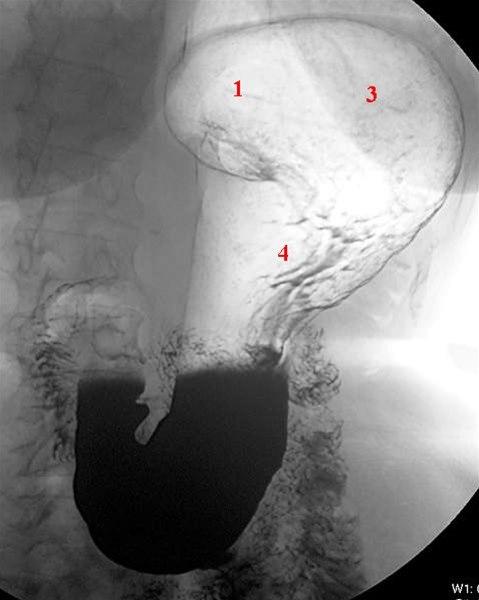

Fra spiserøret kommer maten over i magesekken (ventrikkelen) (se figur). En fylt magesekk rommer vanligvis ca. 1,5 liter. Den ligger øverst i midtre del av bukhulen og har en avlang og krummet fasong. Magesekken har en kort og en lang side, og den smalner av før den går over i tolvfingertarmen (duodenum). Saltsyre og stoffer som starter nedbrytingen av føden (eks. pepsin), lages i slimhinnen i magesekken. Slimhinnen er kledd med et beskyttende slimlag som hindrer saltsyren i å etse hull på magesekken. Den nedsvelgde maten eltes ved at magesekken trekker seg sammen og utvider seg (såkalt peristaltisk aktivitet). Tolvfingertarmen har en C-form og er ca. 25 cm lang. Gallegangen og utførselsgangen til bukspyttkjertelen tømmer seg i tolvfingertarmen. Både galle og bukspytt er nødvendig for nedbrytningen av føden i tarmen.

Et magesår oppstår enten i magesekken eller i tolvfingertarmen (se figur). Sår i tolvfingertarmen forekommer ca. 5 ganger så hyppig som sår i magesekken.

Undersøkelsen fremstiller form, posisjon, slimhinnefolder, sammentrekninger og bevegelser av magesekken og øvre del av fordøyelseskanalen (se røntgenbildene over). Undersøkelsen omfatter vanligvis både øsofagus (spiserør = Ø), ventrikkel (V), duodenum (D) og øvre del av tynntarmen. På fagspråket brukes ofte betegnelsen røntgen Ø+V+D. Undersøkelsen foregår med bruk av kontrast og som regel med såkalt dobbelkontrast-metode, det vil si både kontrastvæske og luft. Røntgen av øvre del av magetarm-kanalen gjøres sjeldnere i dag enn før. Gastroskopi er en mer presis undersøkelse og gir anledning til direkte prøvetaking til mikrobiologiske undersøkelser og mikroskopi av vevsprøver (histologi).